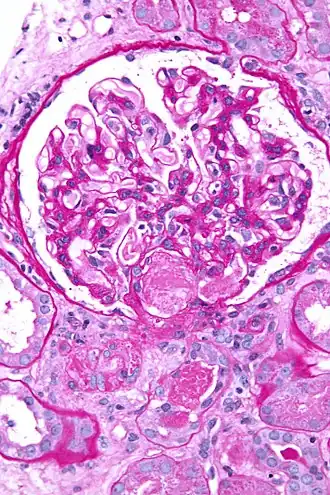

La coagulation intravasculaire disséminée (CIVD), aussi appelée syndrome de défibrination ou coagulopathie de consommation, est une activation pathologique de la coagulation (formation de caillots sanguins). Elle apparaît dans de nombreuses situations pathologiques quand de petits caillots se forment dans les vaisseaux sanguins de tout l'organisme[1]. Ces caillots consomment les facteurs de coagulation. La coagulation normale est ainsi empêchée et des hémorragies (saignements) anormales apparaissent sur la peau (notamment aux sites de prélèvements sanguins), le tube digestif, le tractus respiratoire et les cicatrices chirurgicales. Les petits caillots perturbent aussi le flux sanguin vers les organes (comme les reins) et entraînent une perturbation de leur fonctionnement[2].

- phénomènes thrombotiques : oblitération des petits vaisseaux ;

- des manifestations thrombotiques : thromboses veineuses profondes, infarctus viscéraux, purpura nécrotique, gangrènes distales ;